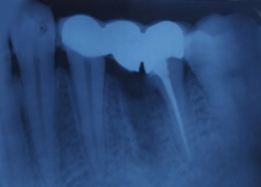

Immediate Post-Surgical IOPAR

Pre-OP IOPAR